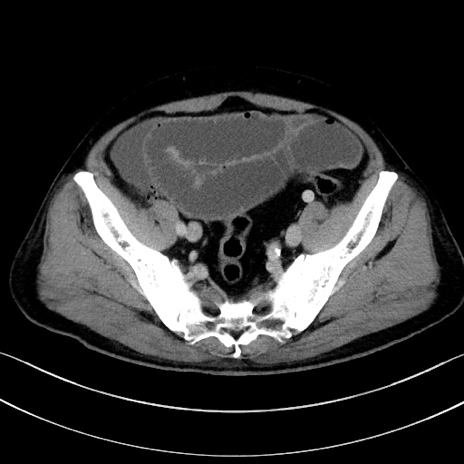

症例

冠状断像